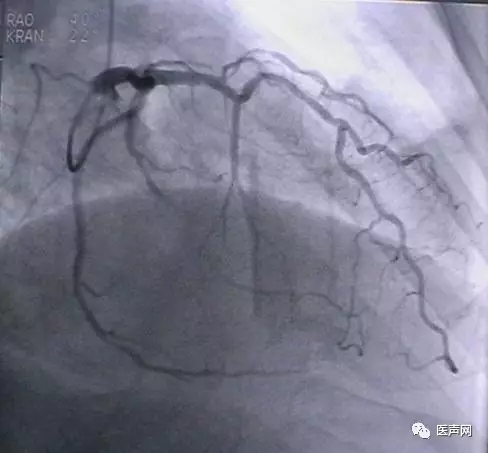

病例4:LAD PCI术后,对角支远端病变

此病变上次PCI不成功,因为LAD有支架,导丝穿过支架网眼入对角支有困难(对角支发出角度很大,成直角(箭头所示)。此次不再尝试,要学会放弃。

见下图: